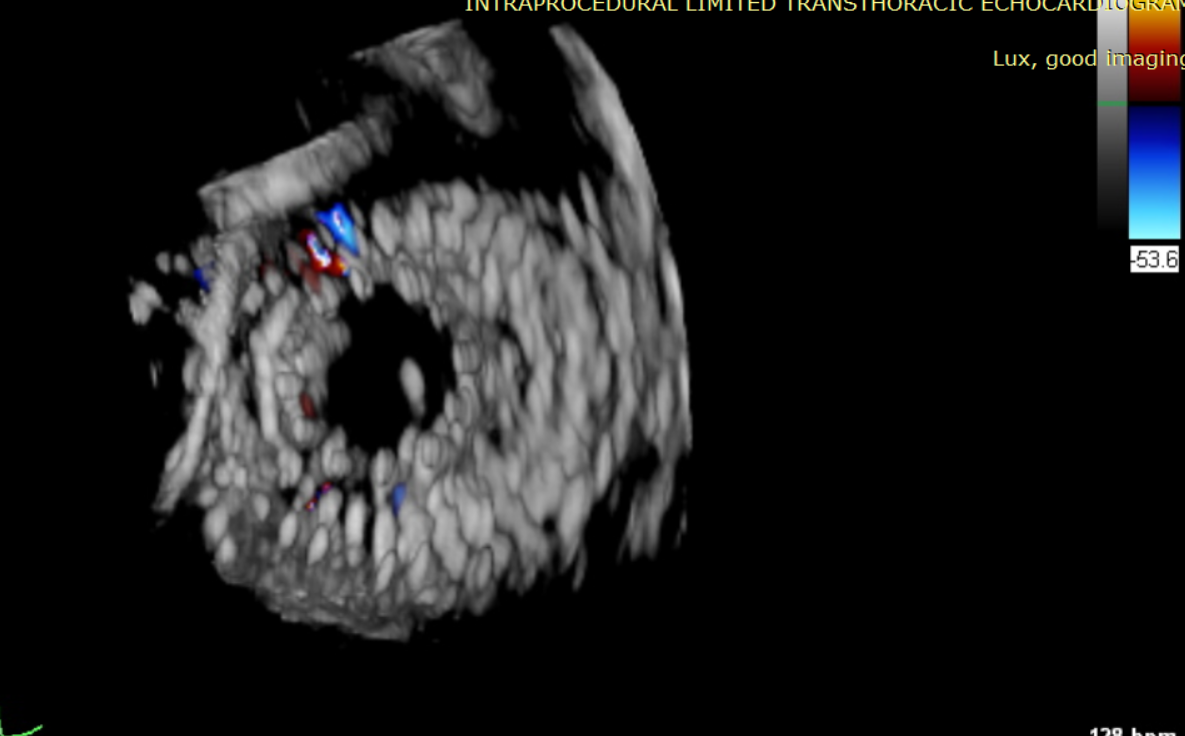

術(shù)中輸送器在超聲引導(dǎo)下調(diào)整位置

術(shù)后超聲提示僅殘余輕微瓣周漏